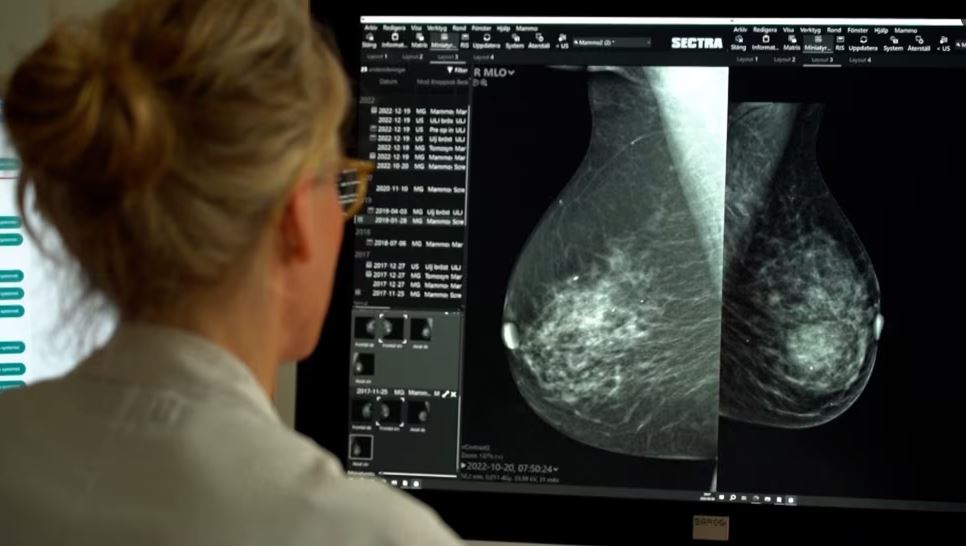

Inteligjenca artificiale mund t’i identifikojë gratë që janë të rrezikuara nga kanceri në gji, disa vjet para se të diagnostikohen, ka thënë Instituti Norvegjez i Shëndetit Publik të martën.

Pesë hulumtuesve të këtij Instituti, Universitetit të Kalifornisë dhe Universitetit të Uashingtonit, u është dhënë qasje në programin komercial të inteligjencës artificiale, i cili në mënyrë retroaktive ka analizuar mamografitë e 116.495 grave që kanë marrë pjesë në programin norvegjez në periudhën 2004 – 2018.

Algoritmi ka arritur të verifikojë se cilat gra kanë pasur rrezik më të madh të zhvillimit të kancerit në gji, madje edhe se cili prej gjinjve ka qenë më i rrezikuar, katër deri në gjashtë vjet para diagnostikimit.

“Ne e kemi vërejtur se gjiri që ka zhvilluar kancer, ka pasur pikë në sistem dyfish më shumë, sesa gjiri tjetër”, ka thënë Solveig Hofvind, gruaja që udhëheq programin për detektim të kancerit në gji përmes programit me inteligjencë artificiale.

“Studimi tregon se algoritmet që tashmë janë të qasshme në treg mund të përdoren për të zhvilluar programe detektimi edhe më të personalizuara”, ka thënë ajo, raporton REL.